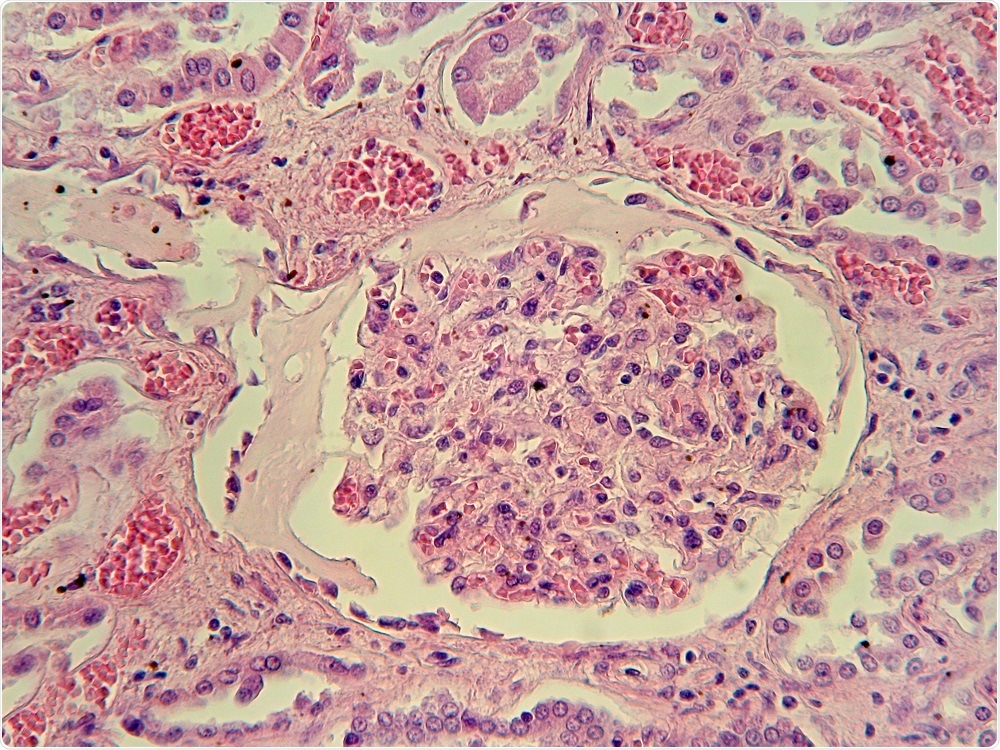

Credit: Jubal Harshaw/Shutterstock.com

Alport Syndrome is a hereditary kidney disease that affects the glomerular basement membrane within the filtration system of the kidney. This allows blood and proteins to escape into the urine and ultimately leads to end-stage kidney disease and hearing loss.

Since trimer formation is necessary for collagen IV to be incorporated into the glomerular basement membrane in the kidney, the mutation results in the membrane becoming leaky.

It no longer forms a physical barrier against leakage of blood components into the urine. In order to cure Alport Syndrome, a treatment is needed to restore collagen IV functionality.